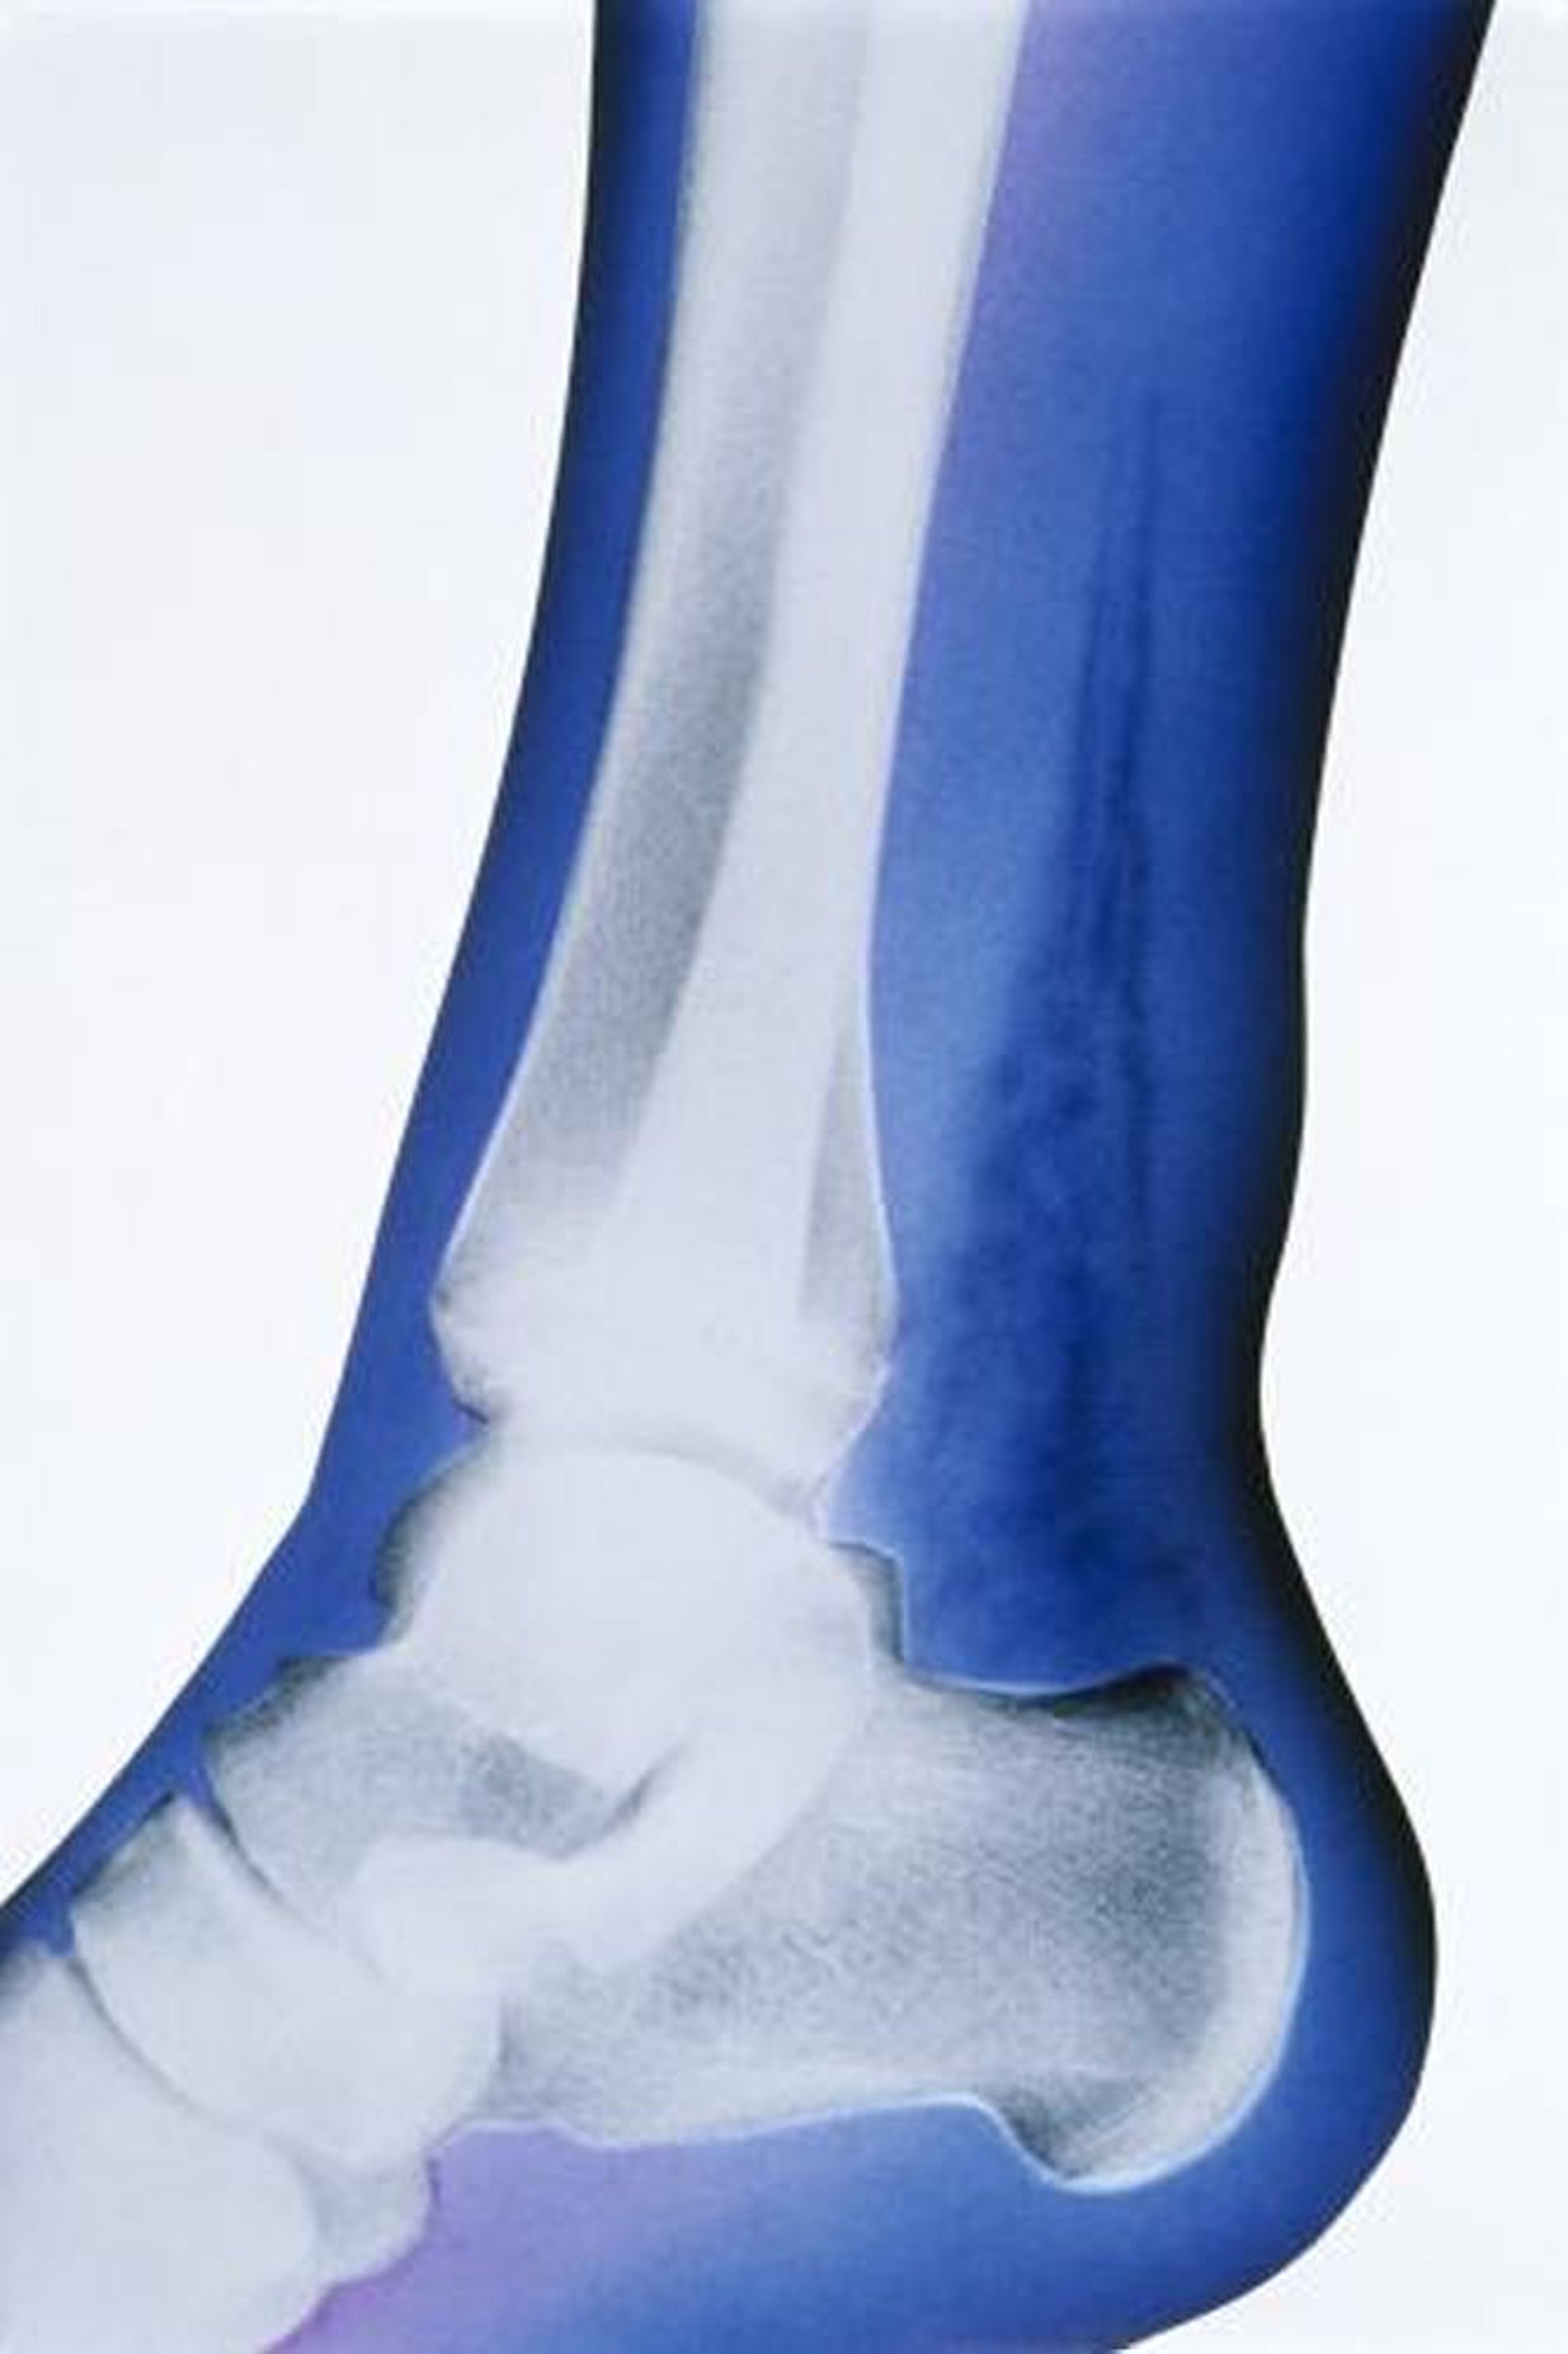

Infection nécrosante des tissus mous (RX)

Dans cette radiographie artificiellement colorée, le signe saillant est la présence de gaz des tissus mous, indiquée par les densités très radiotransparentes au-dessus du calcanéum et postérieures au tibia et au péroné.